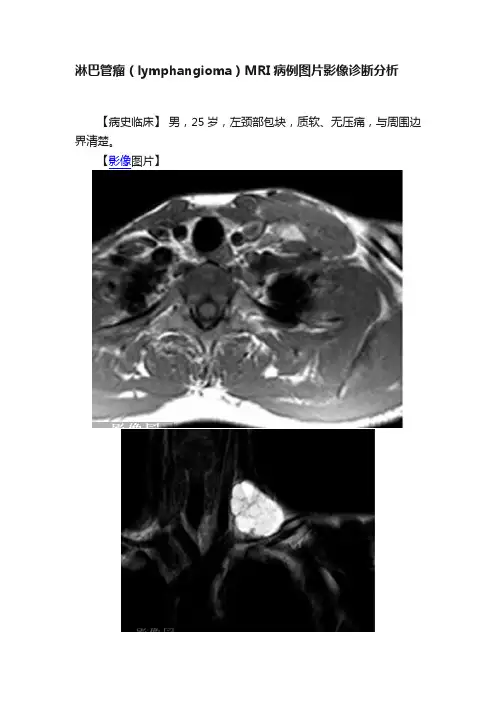

淋巴管瘤(lymphangioma)MRI病例图片影像诊断分析【病史临床】男,25岁,左颈部包块,质软、无压痛,与周围边界清楚。

【影像图片】以上三幅图片分别为MRI横断T1WI 、冠状T2WI及T1WI增强【影像表现】左锁骨上窝见囊性病变,T1WI为低信号,T2WI为高信号,内部信号略不均匀,可见多个线样细分隔,病灶与周围组织分界尚可,增强扫描分隔呈轻度强化。

【诊断】淋巴管瘤(病理确诊)。

镜下见大量大小不等的圆形或不规则形管腔,管腔内衬内皮细胞,腔内未见血细胞成份,无增生内皮细胞团,周围为脂肪和纤维组织。

【鉴别诊断】血管瘤【讨论】淋巴管瘤(lymphangioma)多见于儿童,好发于口腔、颈部、腋窝等部位,属于先天性淋巴管发育畸形。